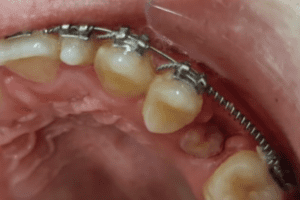

Dopo un’attenta analisi radiografica, abbiamo optato per un trattamento ortodontico che ci ha permesso, grazie ad una molla, di creare lo spazio sufficiente per l’eruzione del 25

Successivamente, in combinazione con la terapia precedentemente stabilita, abbiamo optato per una esposizione con elettrobisturi in modo da permettere al dente la sua normale eruzione. Questa procedura consente un approccio meno invasivo, meno doloroso, previene il sanguinamento, evita la diffusione di batteri e protegge meccanicamente la struttura tissutale; la cicatrizzazione inoltre sarà più rapida e non sarà necessario l’utilizzo di punti di sutura. Il paziente avrà così un recupero più rapido e con maggior confort.